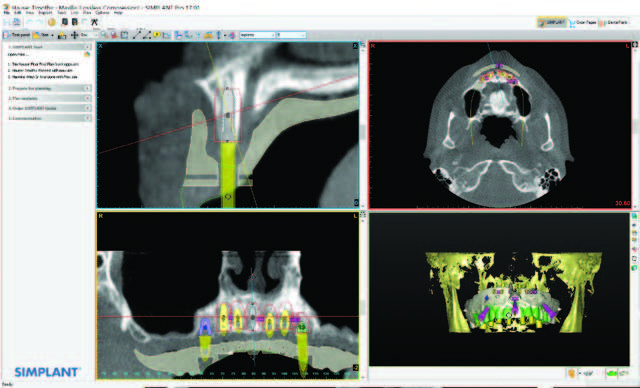

After evaluation of their finances and budget, a treatment was reverse engineered to provide them with a solution. While this patient was communicative and able to carry on a conversation, the issues related to patient care in the post-treatment phase had to be engineered into the prosthetic design. Records were taken, including photographs, study models, bite registrations, CBCT scans with reformatting, and a prosthetically driven implant placement. In order to properly set up this rehabilitation, the patient’s vertical dimension of occlusion (VDO) would be restored. This case would be sequenced to treat the mandibular arch first and then the maxillary arch. The use of 3DDX software (3D Diagnostix) for reformatting the CBCT scan, “fine-tuning” the doctors’ virtual implant placement in coDiagnostX implant planning software (Dental Wings), and the construction of surgical guides was an invaluable adjunct performed by 3DDX and an integral part of the reconstructive team’s effort. The CBCT scan was reformatted to trace nerves in each slice and allow for implant placement virtually within the mandible and, later, in the maxilla. This would ensure that the amount of required osteoplasty at each tooth site could be measured and that osteoplasty would be performed accurately at each root position (Figure 3).

The maxillary arch surgery began after the mandibular arch had healed. The full maxillary edentulation was also done using Piezosurgery and Physics Forceps. As seen in Figure 9, the lingual beak and labial bumper atraumatically “lift” the tooth out of the socket while maintaining the buccal plate. If sectioning of the tooth is required, or if purchase points need to be created for the forceps beak, then this forceps technique can allow for efficient root removal. After the extractions, the sockets were grafted with LifeNetHealth bone (Salvin Dental Specialties), and Mem-Lok type I collagen fiber membranes (BioHorizons) were used over the grafted maxilla due to the need to maintain graft coverage for 26 to 38 weeks. This material was also chosen because of its macromolecular pore size and its easy adaptation to the surgical site. After healing for 4 months, the maxillary implants were virtually planned using a new CBCT scan that first scanned the denture in with fiduciary markers (Suremark) placed and then the denture was scanned separately. This dual scan protocol (as directed by 3DDX) permits deluxe reformatting so that implants can be planned with the upper denture in a separate color, allowing for proper 3-D placement of implants within the confines of the approved occlusal construct (Figure 10). After fine-tuning services, a mucosal- born surgical guide was fabricated with maxillary implants placed for the most optimal A-P spread. The guide tubes, stabilization pins, and quality control were done by 3DDX (Figure 11). The bilateral subantral sinus augmentation was not done in order to accommodate the grandparents’ budget. The maxillary arch was grafted, and an immediate denture was delivered.